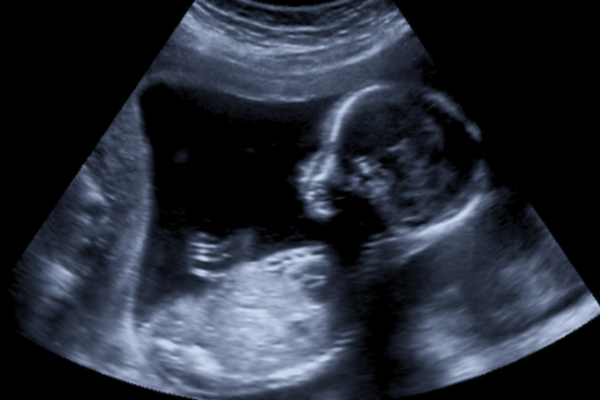

Rahim İçi Gelişme Geriliği teşhisi, muayenelerde rahmin küçük saptanması ve ultrasonografide bebeğin olması gerekenden daha küçük olması ile konulur. Ancak son adet tarihinin tam olarak bilinmemesi veya rutin kontrollerin aksatılması yanlış teşhis koyulmasına sebebiyet verebilir. Bu nedenle gelişme geriliğinden şüphelenen hekimler, bebeğin baş çevresi, baş çapı, karın çevresi ve uyluk kemiği ölçümlerini bir arada değerlendirir. Eğer sonraki kontrollerde de gelişme geriliği artarak devam ediyor ise kesin tanı koymak mümkündür denebilir. Bazı durumlarda bebeğin aile yapısı (genetik) nedeniyle olması gerekenden küçük olması, yanlış teşhis koyulmasına neden olabiliyor.